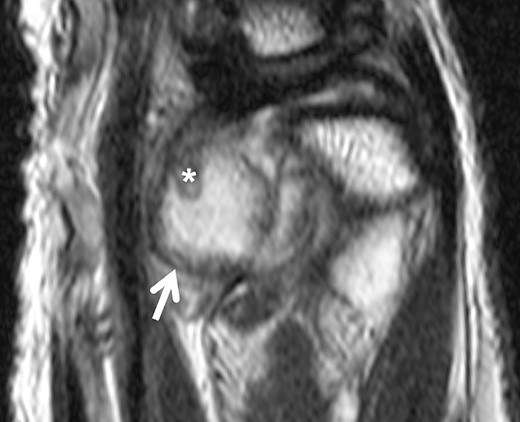

MRI scan revealed suspicion of ganglion cyst formation. The images (Figs 1 and 2) depicted a palmar-directed mass originating from the DRUJ with a transverse diameter measuring a maximum of 12 x 17 mm. The mass exhibited a predominant fluid isointense internal signal, accompanied by marginal signal depressions on T2-weighted sequence. These depressions within the suspected ganglion raised suspicion of diffuse-type tenosynovial giant cell tumor. The mass had contact to the flexor tendons at the level of the DRUJ. No pathological bone marrow edema was observed.

Axial slice of a fat suppressed PD Dixon—synovial capsular proliferation on the volar aspect of the DRUJ (asterix); the capsule is thickened, additionally evidence of hypointense internal structures aside the capsular proliferation.

Sagittal slice of a T2-weighted fast-spin echo sequence of the DRUJ—well-defined hyperintense lesion on the volar aspect of the DRUJ; capsular blooming artifact (short arrow); hypointense, internal structure within the distended DRUJ (asterix), chondromatosis foci accordingly.

Our case presented an intra-articular SC with direct infiltration of the DRUJ, where preoperative MRI scans (Figs 1 and 2) did not reveal evidence of calcified bodies, bone bruise, or periosteal reaction. Therefore, the accurate diagnosis was suspected intraoperatively and confirmed by histopathological examination. Similar discoveries during surgery were documented by Misawa et al. and Rogachefsky et al. in the literature [3, 4]. Kim et al. reported in 2015 that no free chondral bodies were found in the surrounding tissue of their case [5].